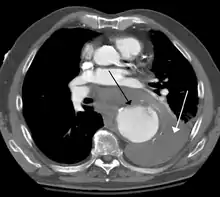

A thoracic aortic aneurysm is an aortic aneurysm that presents primarily in the thorax.

A thoracic aortic aneurysm is the "ballooning" of the upper aspect of the aorta, above the diaphragm. Untreated or unrecognized they can be fatal due to dissection or "popping" of the aneurysm leading to nearly instant death. Thoracic aneurysms are less common than an abdominal aortic aneurysm.[2] However, a syphilitic aneurysm is more likely to be a thoracic aortic aneurysm than an abdominal aortic aneurysm. This condition is commonly treated via a specialized multidisciplinary approach with both vascular surgeons and cardiac surgeons.

Thoracic aortic aneurysm is defined as a cross-sectional diameter exceeding the following cutoff:

A diameter of 3.5 cm is generally considered dilated.[8] However, average values vary with age and size of the reference population, as well as different segments of the aorta.